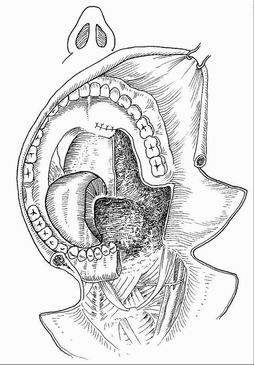

BPTM - Mandibulární split

Mandibulotomie

- Mediální

- Paramediální

- (Para)laterální

Kost nepostižená tumorem